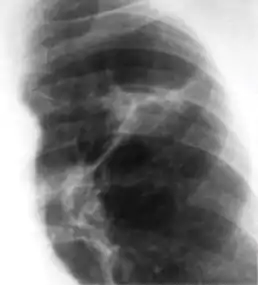

Chest x-ray of Ghon's complex of active tuberculosis

Ghon's complex is a lesion seen in the lung that is caused by tuberculosis.[1][2] The lesions consist of a Ghon focus along with pulmonary lymphadenopathy within a nearby pulmonary lymph node. A Ghon's complex retains viable bacteria, making them sources of long-term infection, which may reactivate and trigger secondary tuberculosis later in life.[3]

In countries where cow milk infected with Mycobacterium bovis has been eliminated (due to culling of infected cows and pasteurization), primary tuberculosis is usually caused by Mycobacterium tuberculosis and almost always begins in the lungs. Typically, the inhaled bacilli implant in the distal airspaces of the lower part of the upper lobe or the upper part of the lower lobe, usually close to the pleura. As sensitization develops, a 1 to 1.5 cm area of gray-white inflammation with consolidation emerges, known as the Ghon focus. In most cases, the center of this focus undergoes caseous necrosis. Tubercle bacilli, either free or within phagocytes, drain to the regional nodes, which also often caseate. This combination of parenchymal lung lesion and nodal involvement is referred to as the Ghon complex. During the first few weeks, there is also lymphatic and hematogenous dissemination to other parts of the body.

The Ghon complex undergoes progressive fibrosis, often followed by radiologically detectable calcification (Ranke complex), and despite seeding of other organs, no lesions develop. Although they are often confused, Ranke complex and Ghon complex are not synonymous. The Ranke complex is an evolution of the Ghon complex (resulting from further healing and calcification of the lesion).[4][5]